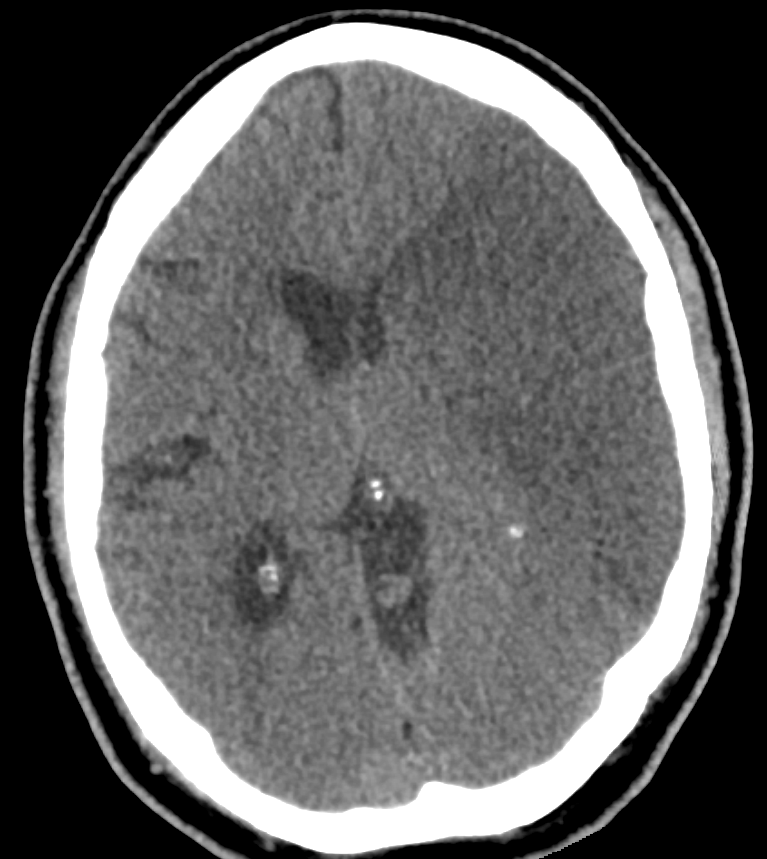

Unter einem malignen Mediainfarkt versteht man ein proximalen Verschluss der Arteria cerebri media, welcher zu einem großvolumigen Infarktareal im Mediastromgebiet führt. Das hierbei entstehende Hirnödem kann bis zur Herniation führen, was zur Bezeichnung eines malignen Infarkts führt.

Bildgebung